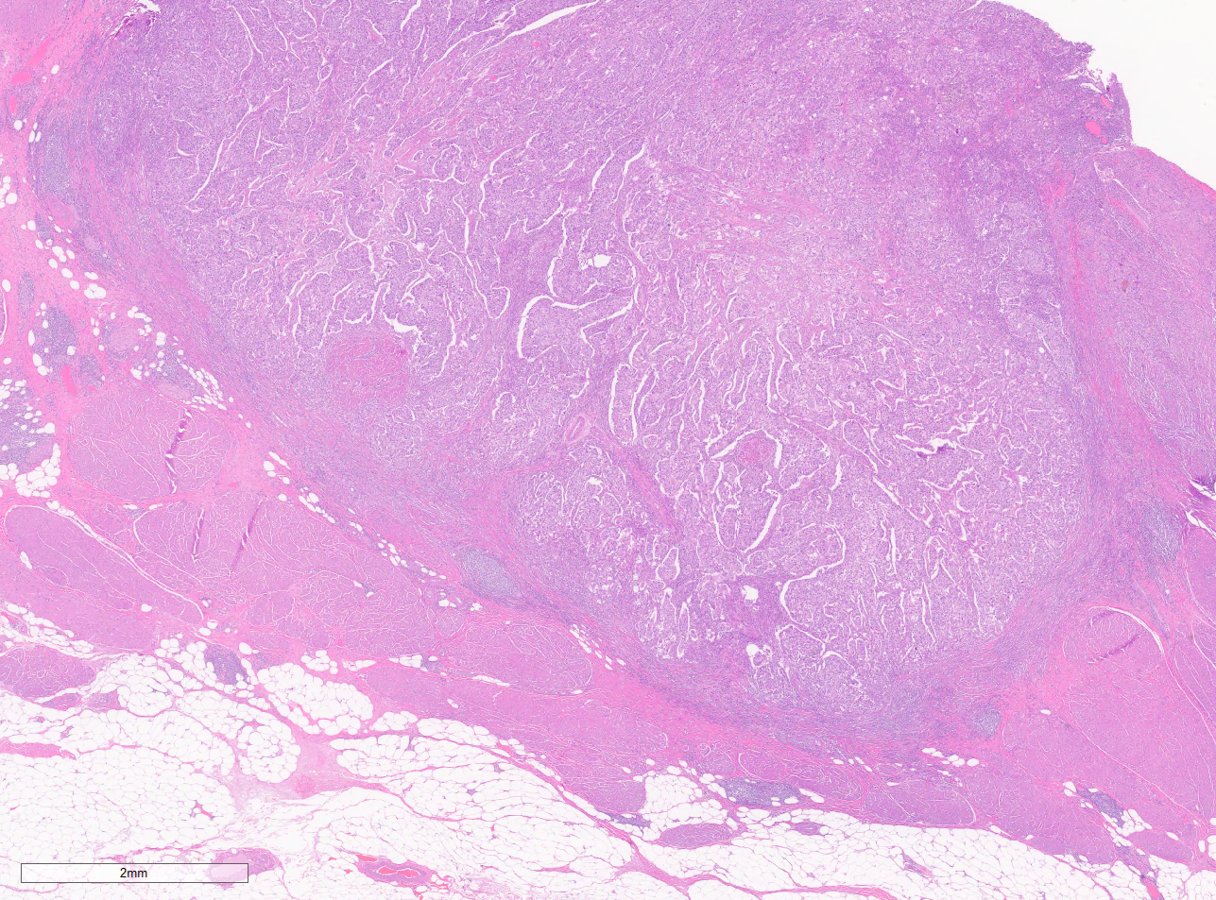

Bladder cancer is typically diagnosed when the urologist looks inside the bladder by doing a cystoscopy and sees an abnormality.

For many patients it's a small, easily removed, low-grade tumor that could be compared to a wart or colon polyp.

But a small number of bladder cancer patients have a more aggressive tumor, which can invade and spread more rapidly to other areas, requiring more aggressive treatment.